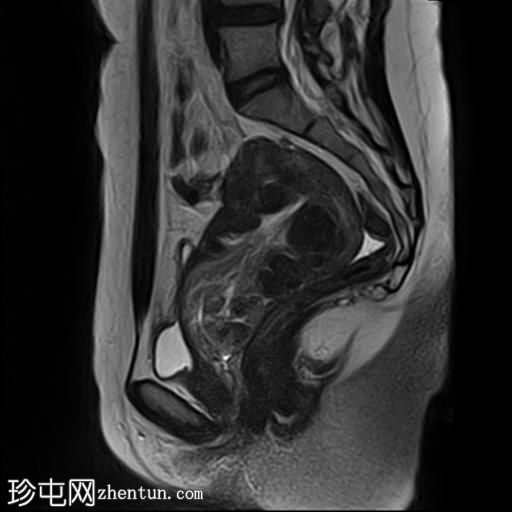

MRI

轴位

T1加权像

子宫增大,前倾后屈,可见多发大小不一、位置各异的壁内肌瘤(主要位于Figo 2、5和6区)。

一个边界清晰的带蒂宫腔内肿块经扩张的宫颈管脱出。T1加权像上呈等信号,T2加权像上呈中低信号,周围环绕着高信号的子宫内膜,静脉注射对比剂后呈明显不均匀强化。

双侧卵巢外观正常,可见小卵泡。

MRI 影像特征最符合带蒂子宫肌瘤经扩张的宫颈管脱垂,并伴有多个子宫肌瘤。